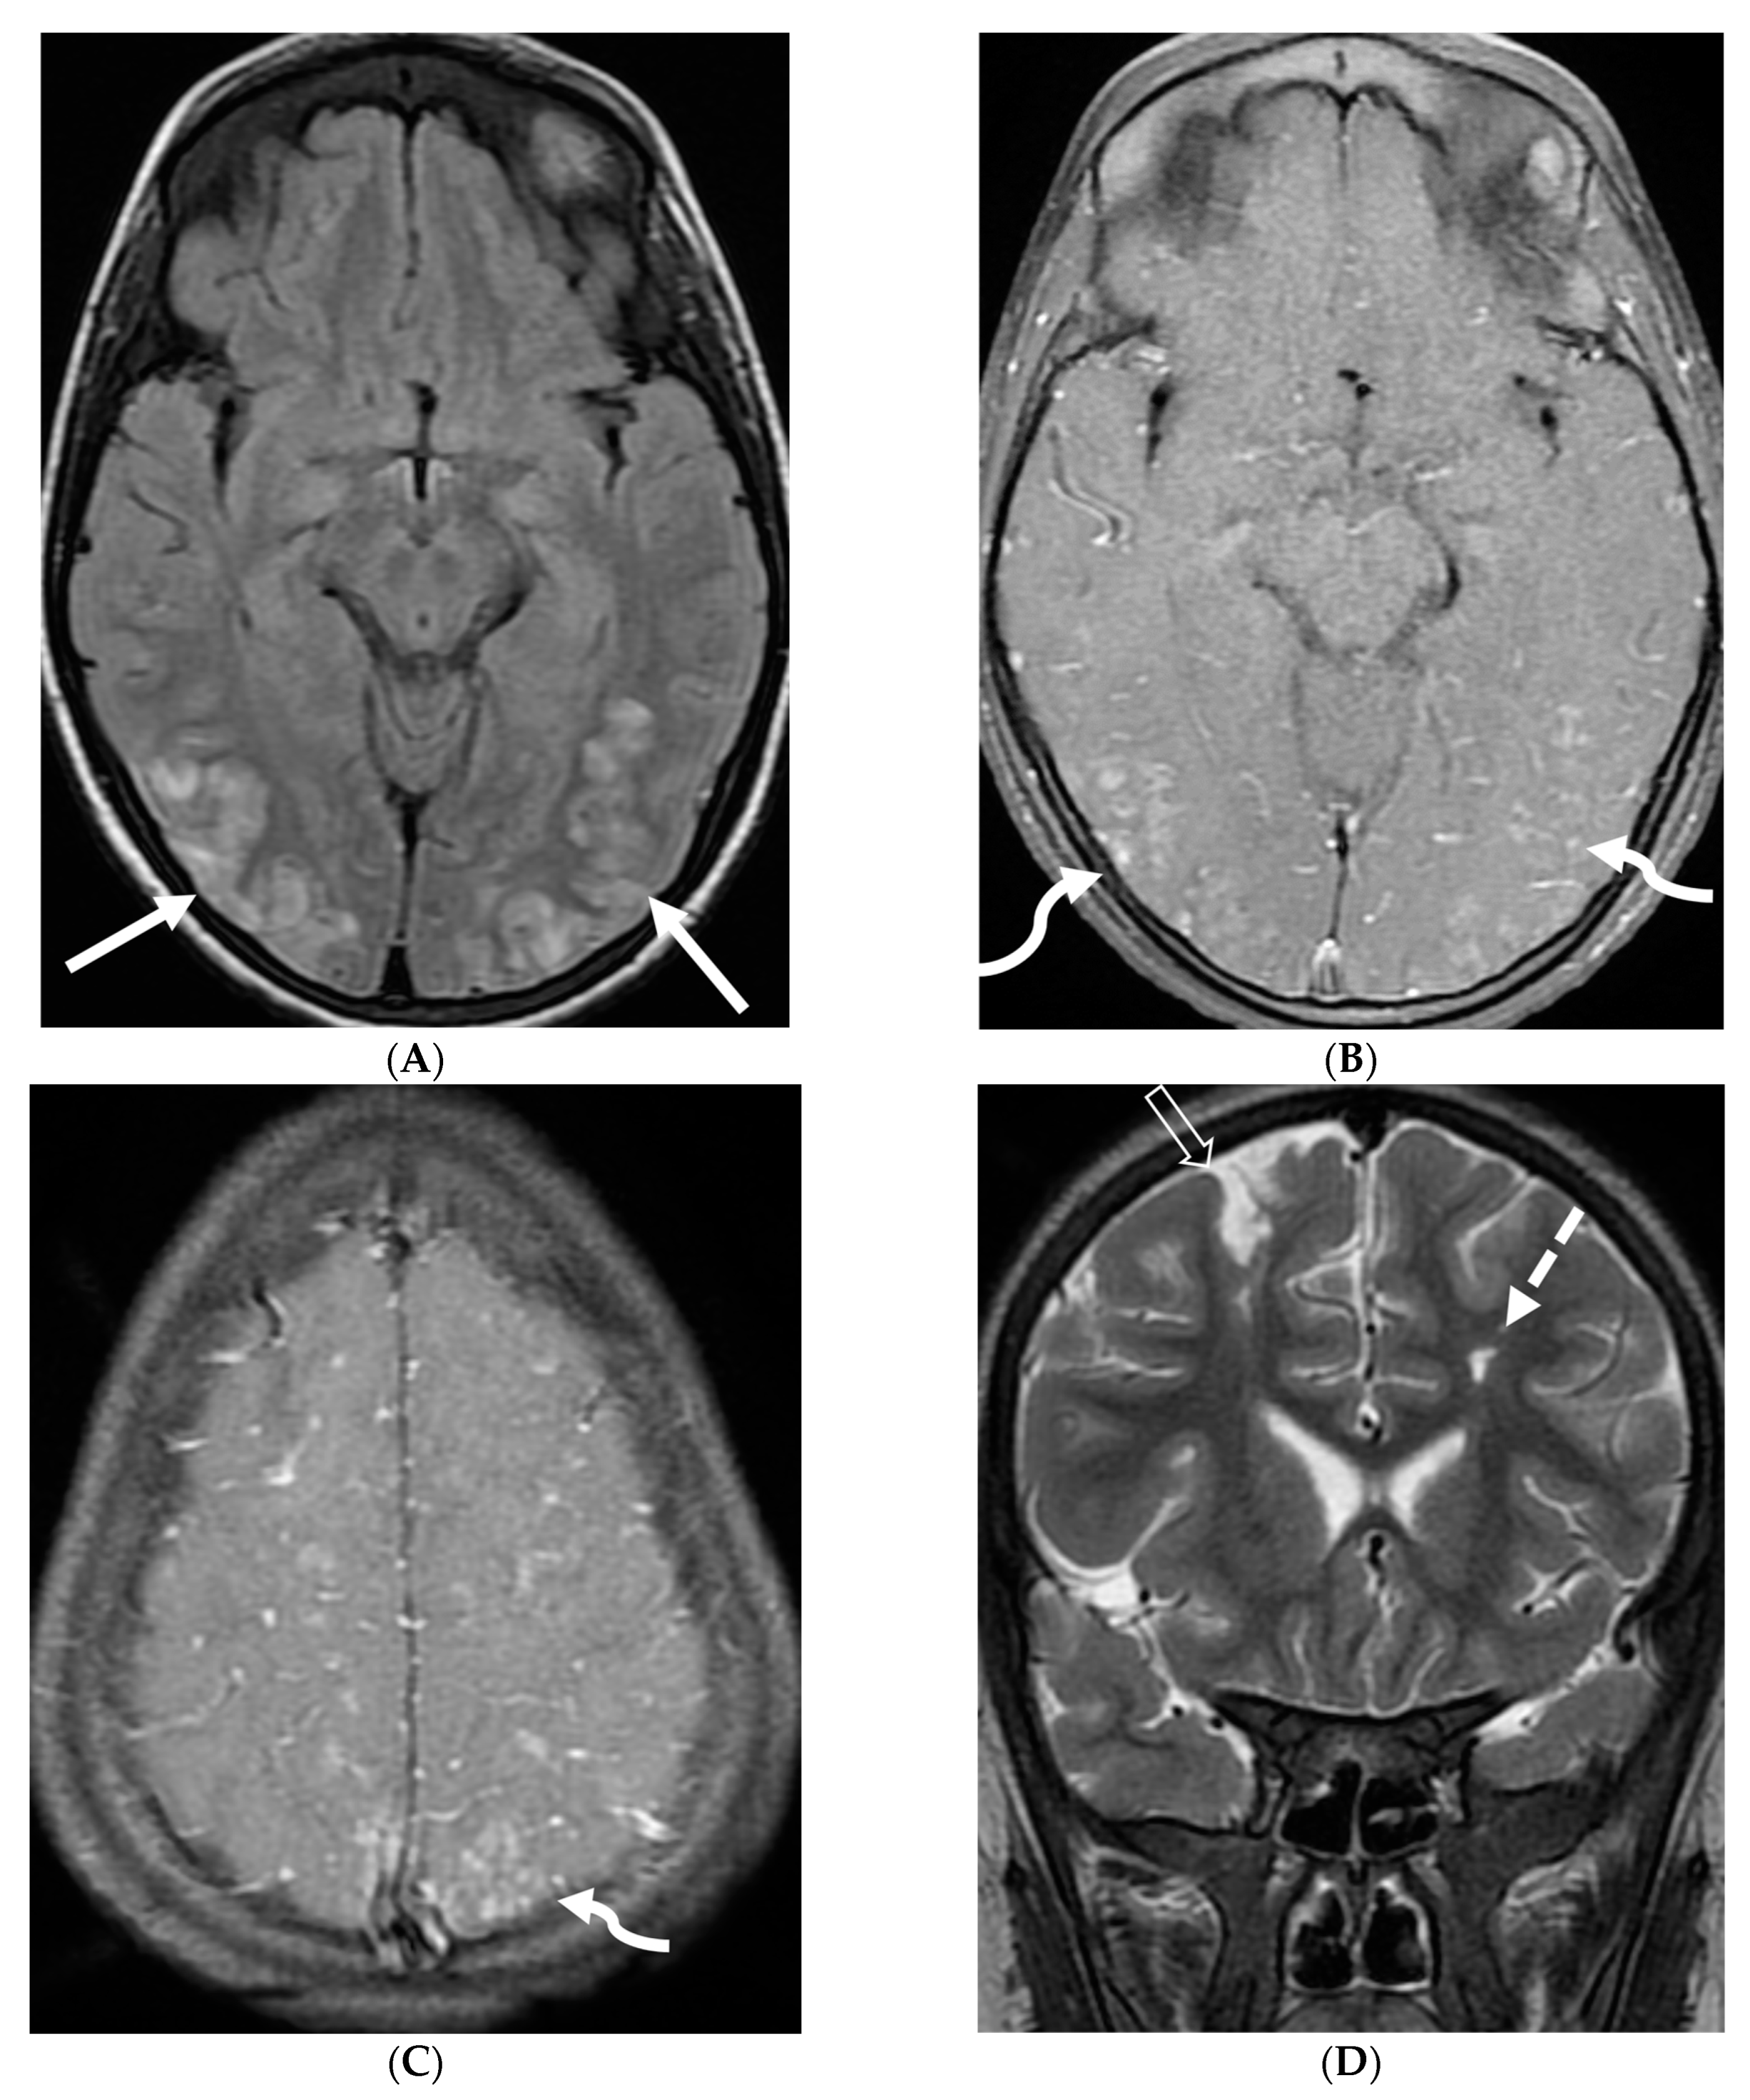

Figure 3.

18-year-old presented with headache, persistent vomiting and weight loss. History of sarcoidosis diagnosed 2 years ago. Axial Fluid Attenuated Inversion Recovery (FLAIR) (A), Axial T1 post contrast (B), Axial T1 inversion recovery post contrast (C) and Coronal Positron Emission Tomograpy (PET) scan (D): There is a heterogeneously enhancing ill-defined area of T2/FLAIR hyperintensity involving the medial aspect of the left globus pallidus (arrows), anterior aspect of the left thalamus and left hypothalamic region. Diffuse enhancement of the basal meninges, tentorium, throughout perisylvian sulci (arrow heads), along the infundibulum, and posteriorly at the craniocervical junction. There is also enhancement along optic nerve sheath (dashed arrows). Features are highly consistent with extensive neurosarcoidosis given the previous history of thoracic sarcoid. PET scan from 2 years earlier demonstrating avid uptake of radiotracer (curved arrows). Radiologically, the differential diagnosis includes tuberculosis and metastatic process. Patient made complete recovery after treatment for sarcoid.